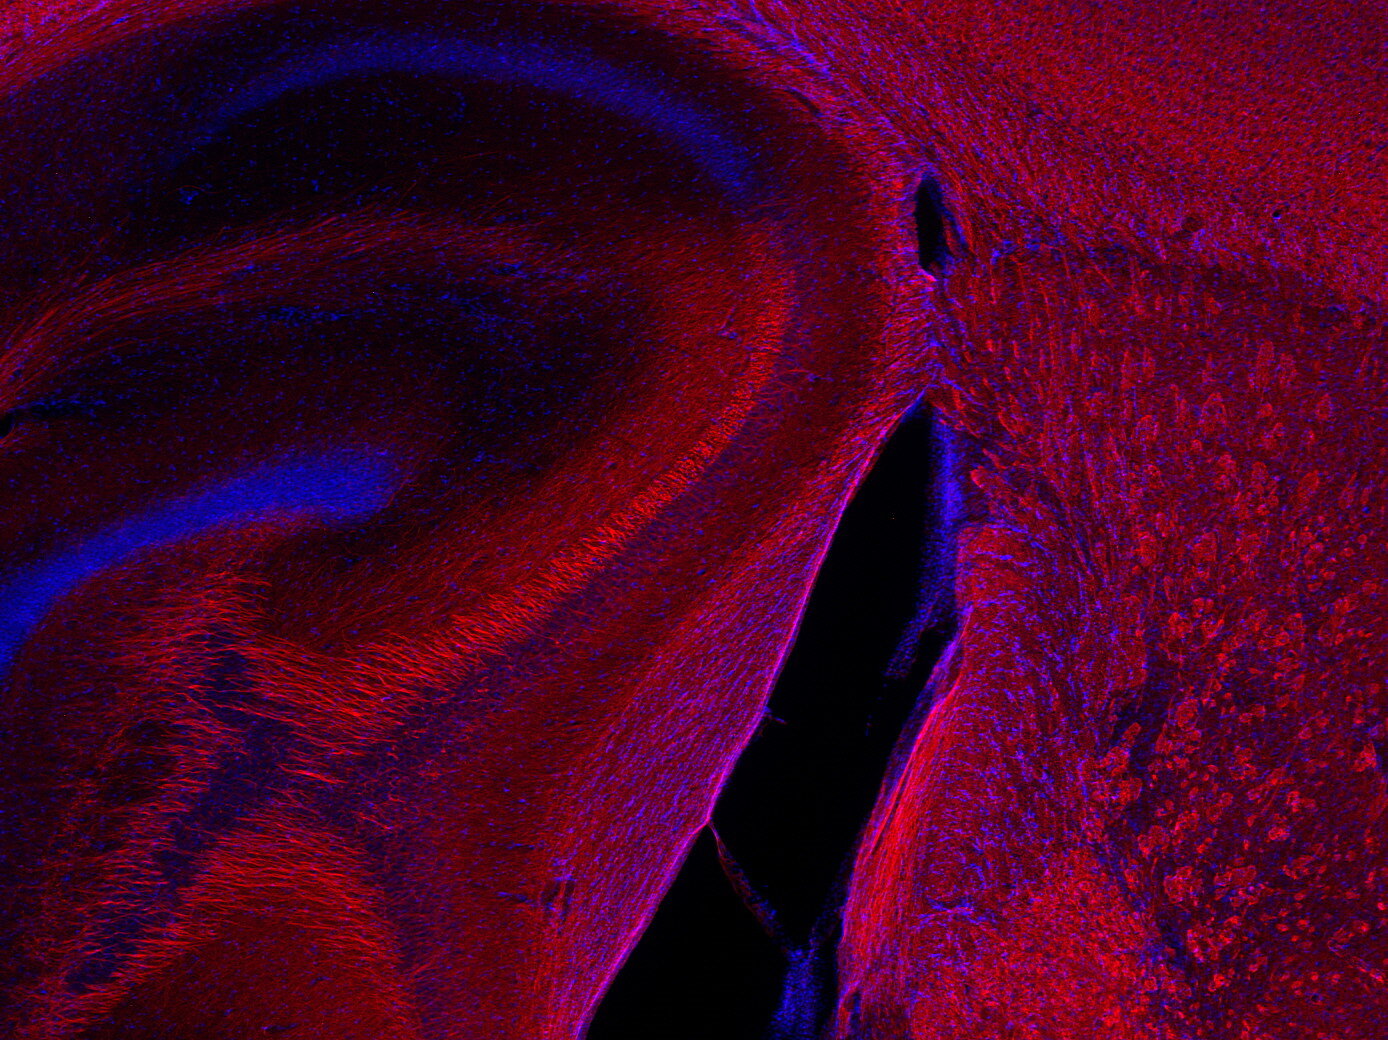

IHC: 1 : 500 up to 1 : 1000 gallery

Immunohistochemistry (IHC) on 4% PFA perfusion fixed tissue with 24h PFA post fixation. Immunoreactivity is usually revealed by fluorescence or a chromogenic substrate. Some antibodies require special fixation methods or antigen retrieval steps. For details, please refer to the ”Remarks” section.

Neurofilaments (NFs) are intermediate filaments essential for providing structural support to neurons, particularly within axons. They play a crucial role in maintaining axonal diameter, which directly influences nerve conduction velocity (1). Neurofilaments are composed of three primary subunits - NF-L (light), NF-M (medium) and NF-H (heavy) – along with an NF-associated protein. In the adult central nervous system (CNS), α-internexin serves as the fourth neurofilament subunit, whereas in the peripheral nervous system (PNS), peripherin takes on this role (2).

Beyond their structural function, neurofilaments are also valuable biomarkers in both research and clinical settings. They are widely used in immunohistochemistry to stain and visualize axons, particularly in peripheral nerves and the CNS. Increased levels of neurofilament proteins in cerebrospinal fluid (CSF) or blood are strongly associated with neurodegenerative diseases, such as amyotrophic lateral sclerosis (ALS), multiple sclerosis (MS), and Alzheimer’s disease (3). In peripheral nerve studies, neurofilament staining is often combined with other markers, such as S100, to provide a more comprehensive assessment of nerve structure and pathology (4).